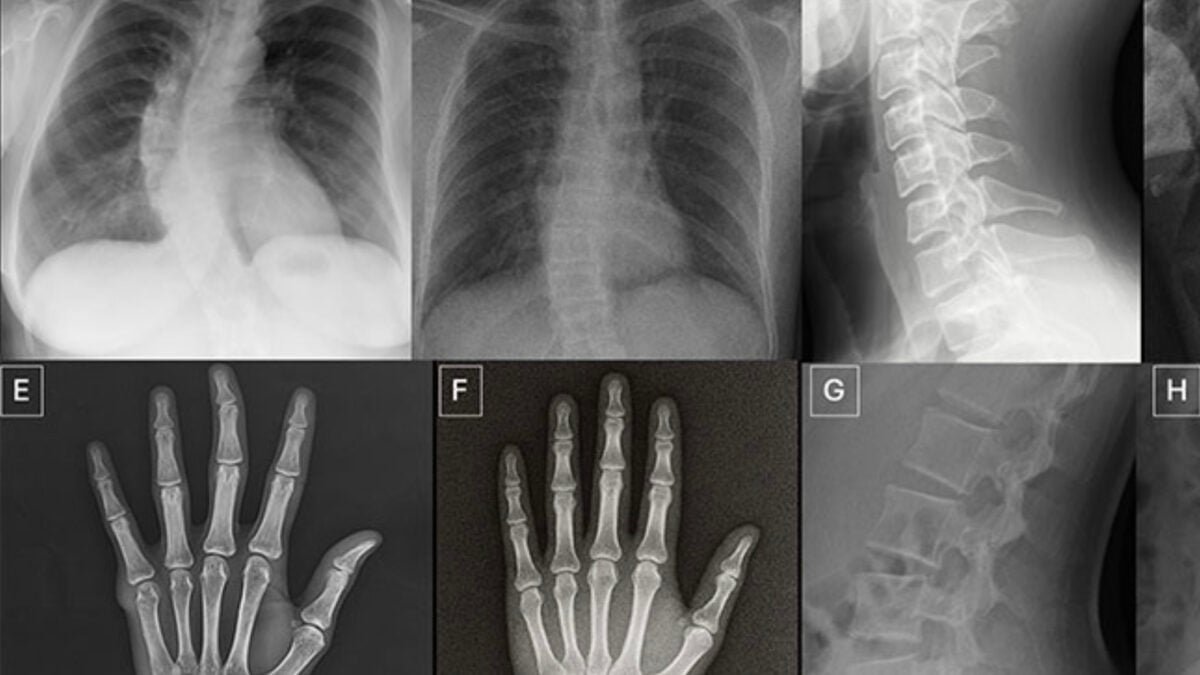

The researchers tested a group of volunteers, 17 practicing radiologists from six countries, requiring them to distinguish real X-rays from AI-generated simulacra in a pool of 264 unique images. The results did not inspire confidence.

The 17 volunteer radiologists Tordjman’s team tested for the study, published Tuesday in the journal Radiology, were exposed to two different datasets. The first asked volunteers to view 154 static X-rays, half real radiographs and half Chat GPT-4O-generated forgeries (77 each). The second trial used a special diffusion model AI trained to produce reliable chest radiographs, called roentgens, which show organs such as the heart and lungs; Volunteers were asked to sort a dataset of 110 images, 55 real and 55 fake.

The study’s 17 individual radiologists, whose depth of professional experience varied (zero to 40 years on the job), ranged from 58% to 92% on ChatGPT-generated images and from 62% to 78% on Roentgen-generated chest X-rays. Age and experience do not seem to be a factor in their accuracy, but, for some reason, musculoskeletal radiologists have proven to be significantly better at detecting fakes than other subspecialists.

Tordjman said he hopes these findings will be used in the future to establish educational datasets and identification tools. “Deepfake medical images often look very accurate,” he said. “The bones are exceedingly smooth, the spine unnaturally straight, the lungs highly symmetrical, the patterns of blood vessels exceedingly uniform, and the fractures appear unusually clean and consistent.”